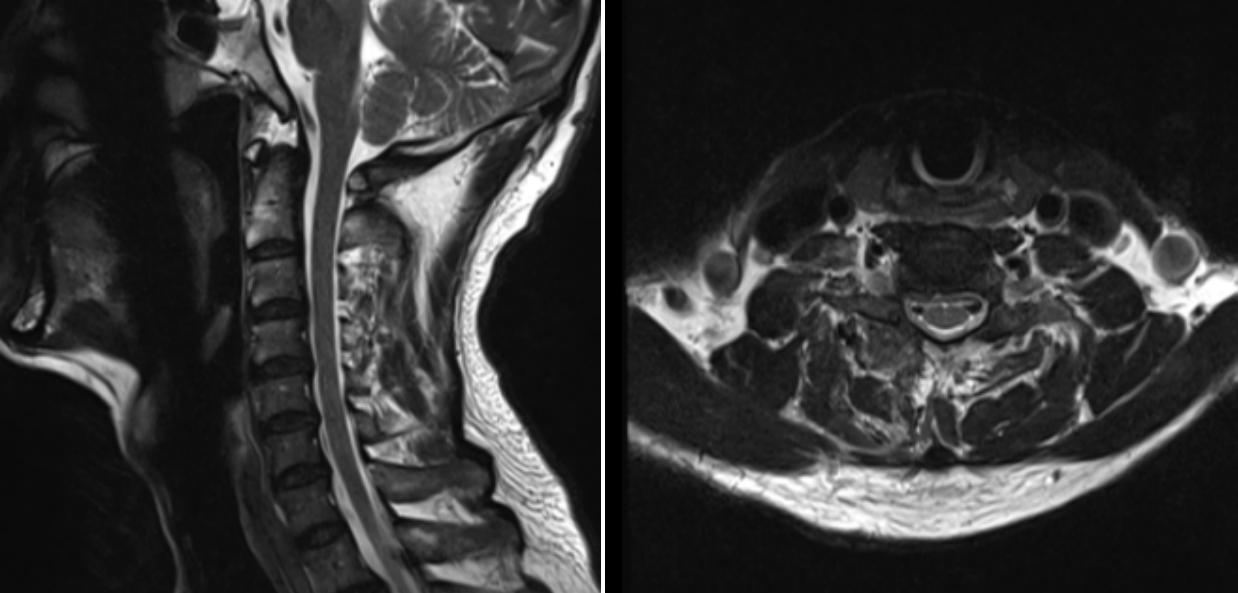

患者,男,65歲,近期飽受右側(cè)上肢疼痛與麻木之苦,歷時三周之久。在外院嘗試保守治療措施,效果不佳,來我院就診。經(jīng)過醫(yī)療團隊周密而細致的檢查,患者被明確診斷為“神經(jīng)根型頸椎病”,精準地指出了其癥狀的根本原因。

術(shù)前MRI圖像

鑒于患者病情的特殊性及復雜性,脊柱外科的朱中蛟專家團隊迅速行動起來,依托前沿醫(yī)療技術(shù),精心制定了治療方案。團隊決定采用當前先進的UBE(單側(cè)雙通道脊柱內(nèi)鏡)技術(shù),實施一場被譽為“鑰匙孔手術(shù)”的微創(chuàng)手術(shù)。此技術(shù)以其創(chuàng)傷小、恢復快的優(yōu)勢,成為治療此類頸椎疾病的理想選擇。